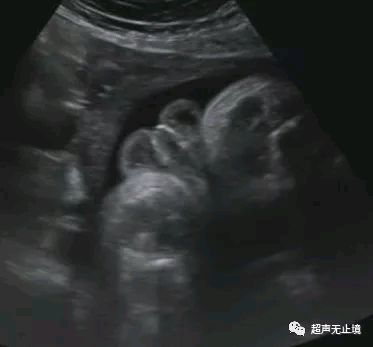

“郁金香征”为胎儿严重尿道下裂表现,代表短小弯曲的阴茎位于分裂的阴囊之间